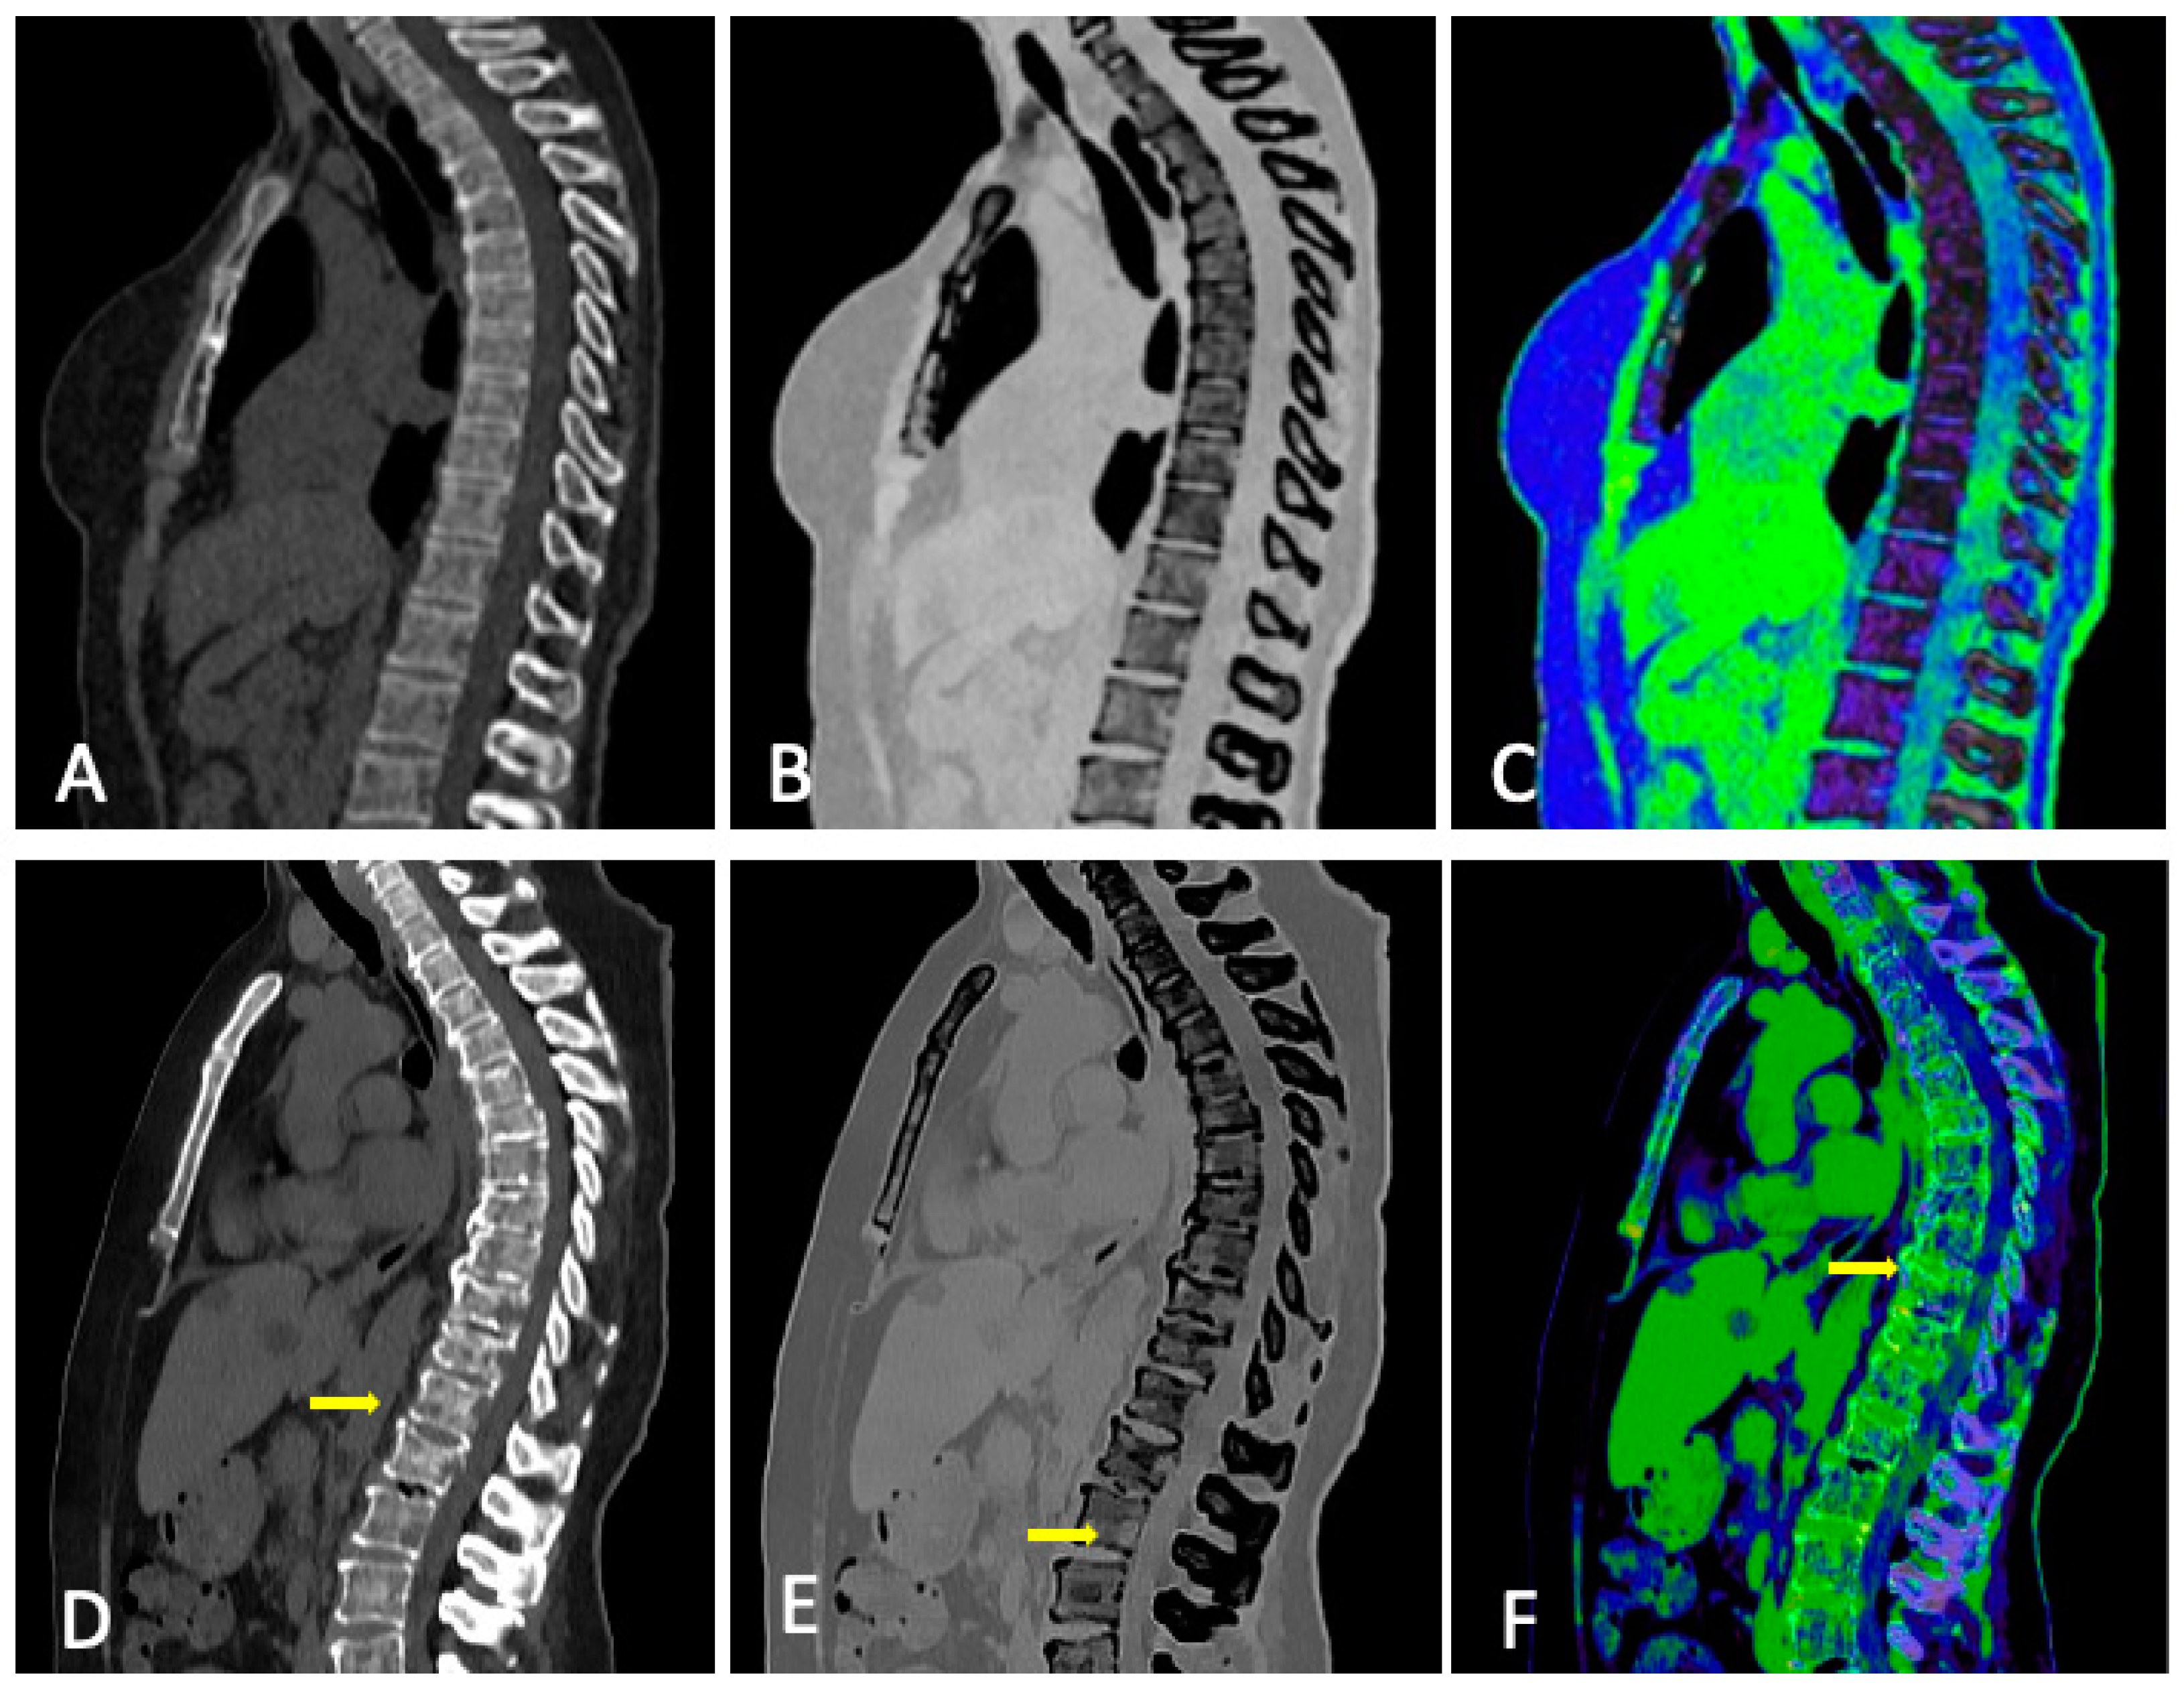

3.3. Role of DECT

3.4. DECT vs. Conventional CT

- Thomas, C.; Schabel, C.; Krauss, B.; Weisel, K.; Bongers, M.; Claussen, C.D.; Horger, M. Dual-Energy CT: Virtual Calcium Subtraction for Assessment of Bone Marrow Involvement of the Spine in Multiple Myeloma. Am. J. Roentgenol. 2015, 204, W324–W331. [Google Scholar] [CrossRef]

- Brandelik, S.C.; Skornitzke, S.; Mokry, T.; Sauer, S.; Stiller, W.; Nattenmüller, J.; Kauczor, H.U.; Weber, T.F.; Do, T.D. Quantitative and Qualitative Assessment of Plasma Cell Dyscrasias in Dual-Layer Spectral CT. Eur. Radiol. 2021, 31, 7664–7673. [Google Scholar] [CrossRef]

- Fervers, P.; Celik, E.; Bratke, G.; Maintz, D.; Baues, C.; Ruffing, S.; Pollman-Schweckhorst, P.; Kottlors, J.; Lennartz, S.; Große Hokamp, N. Radiotherapy Response Assessment of Multiple Myeloma: A Dual-Energy CT Approach with Virtual Non-Calcium Images. Front. Oncol. 2021, 11, 734819. [Google Scholar] [CrossRef]

- Kosmala, A.; Weng, A.M.; Heidemeier, A.; Krauss, B.; Knop, S.; Bley, T.A.; Petritsch, B. Multiple Myeloma and Dual-Energy CT: Diagnostic Accuracy of Virtual Noncalcium Technique for Detection of Bone Marrow Infiltration of the Spine and Pelvis. Radiology 2018, 286, 205–213. [Google Scholar] [CrossRef]

- Gu, R.; Amlani, A.; Haberland, U.; Hodson, D.; Streetly, M.; Antonelli, M.; Dregely, I.; Goh, V. Correlation between Whole Skeleton Dual Energy CT Calcium-Subtracted Attenuation and Bone Marrow Infiltration in Multiple Myeloma. Eur. J. Radiol. 2022, 149, 110223. [Google Scholar] [CrossRef] [PubMed]

- Werner, S.; Krauss, B.; Horger, M. Dual-Energy CT-Based Bone Marrow Imaging in Multiple Myeloma: Assessment of Focal Lesions in Relation to Disease Status and MRI Findings. Acad. Radiol. 2022, 29, 245–254. [Google Scholar] [CrossRef] [PubMed]

- Fervers, P.; Glauner, A.; Gertz, R.; Täger, P.; Kottlors, J.; Maintz, D.; Borggrefe, J. Virtual Calcium-Suppression in Dual Energy Computed Tomography Predicts Metabolic Activity of Focal MM Lesions as Determined by Fluorodeoxyglucose Positron-Emission-Tomography. Eur. J. Radiol. 2021, 135, 109502. [Google Scholar] [CrossRef] [PubMed]

- Kosmala, A.; Weng, A.M.; Krauss, B.; Knop, S.; Bley, T.A.; Petritsch, B. Dual-Energy CT of the Bone Marrow in Multiple Myeloma: Diagnostic Accuracy for Quantitative Differentiation of Infiltration Patterns. Eur. Radiol. 2018, 28, 5083–5090. [Google Scholar] [CrossRef] [PubMed]